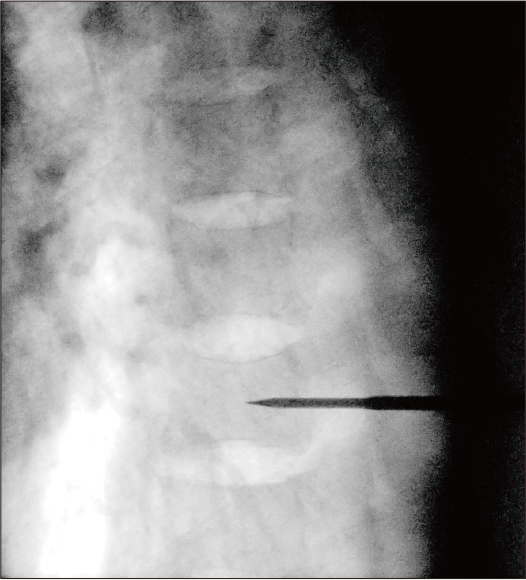

General processing

Dose: 8.4mA

After applying Dynamic processing